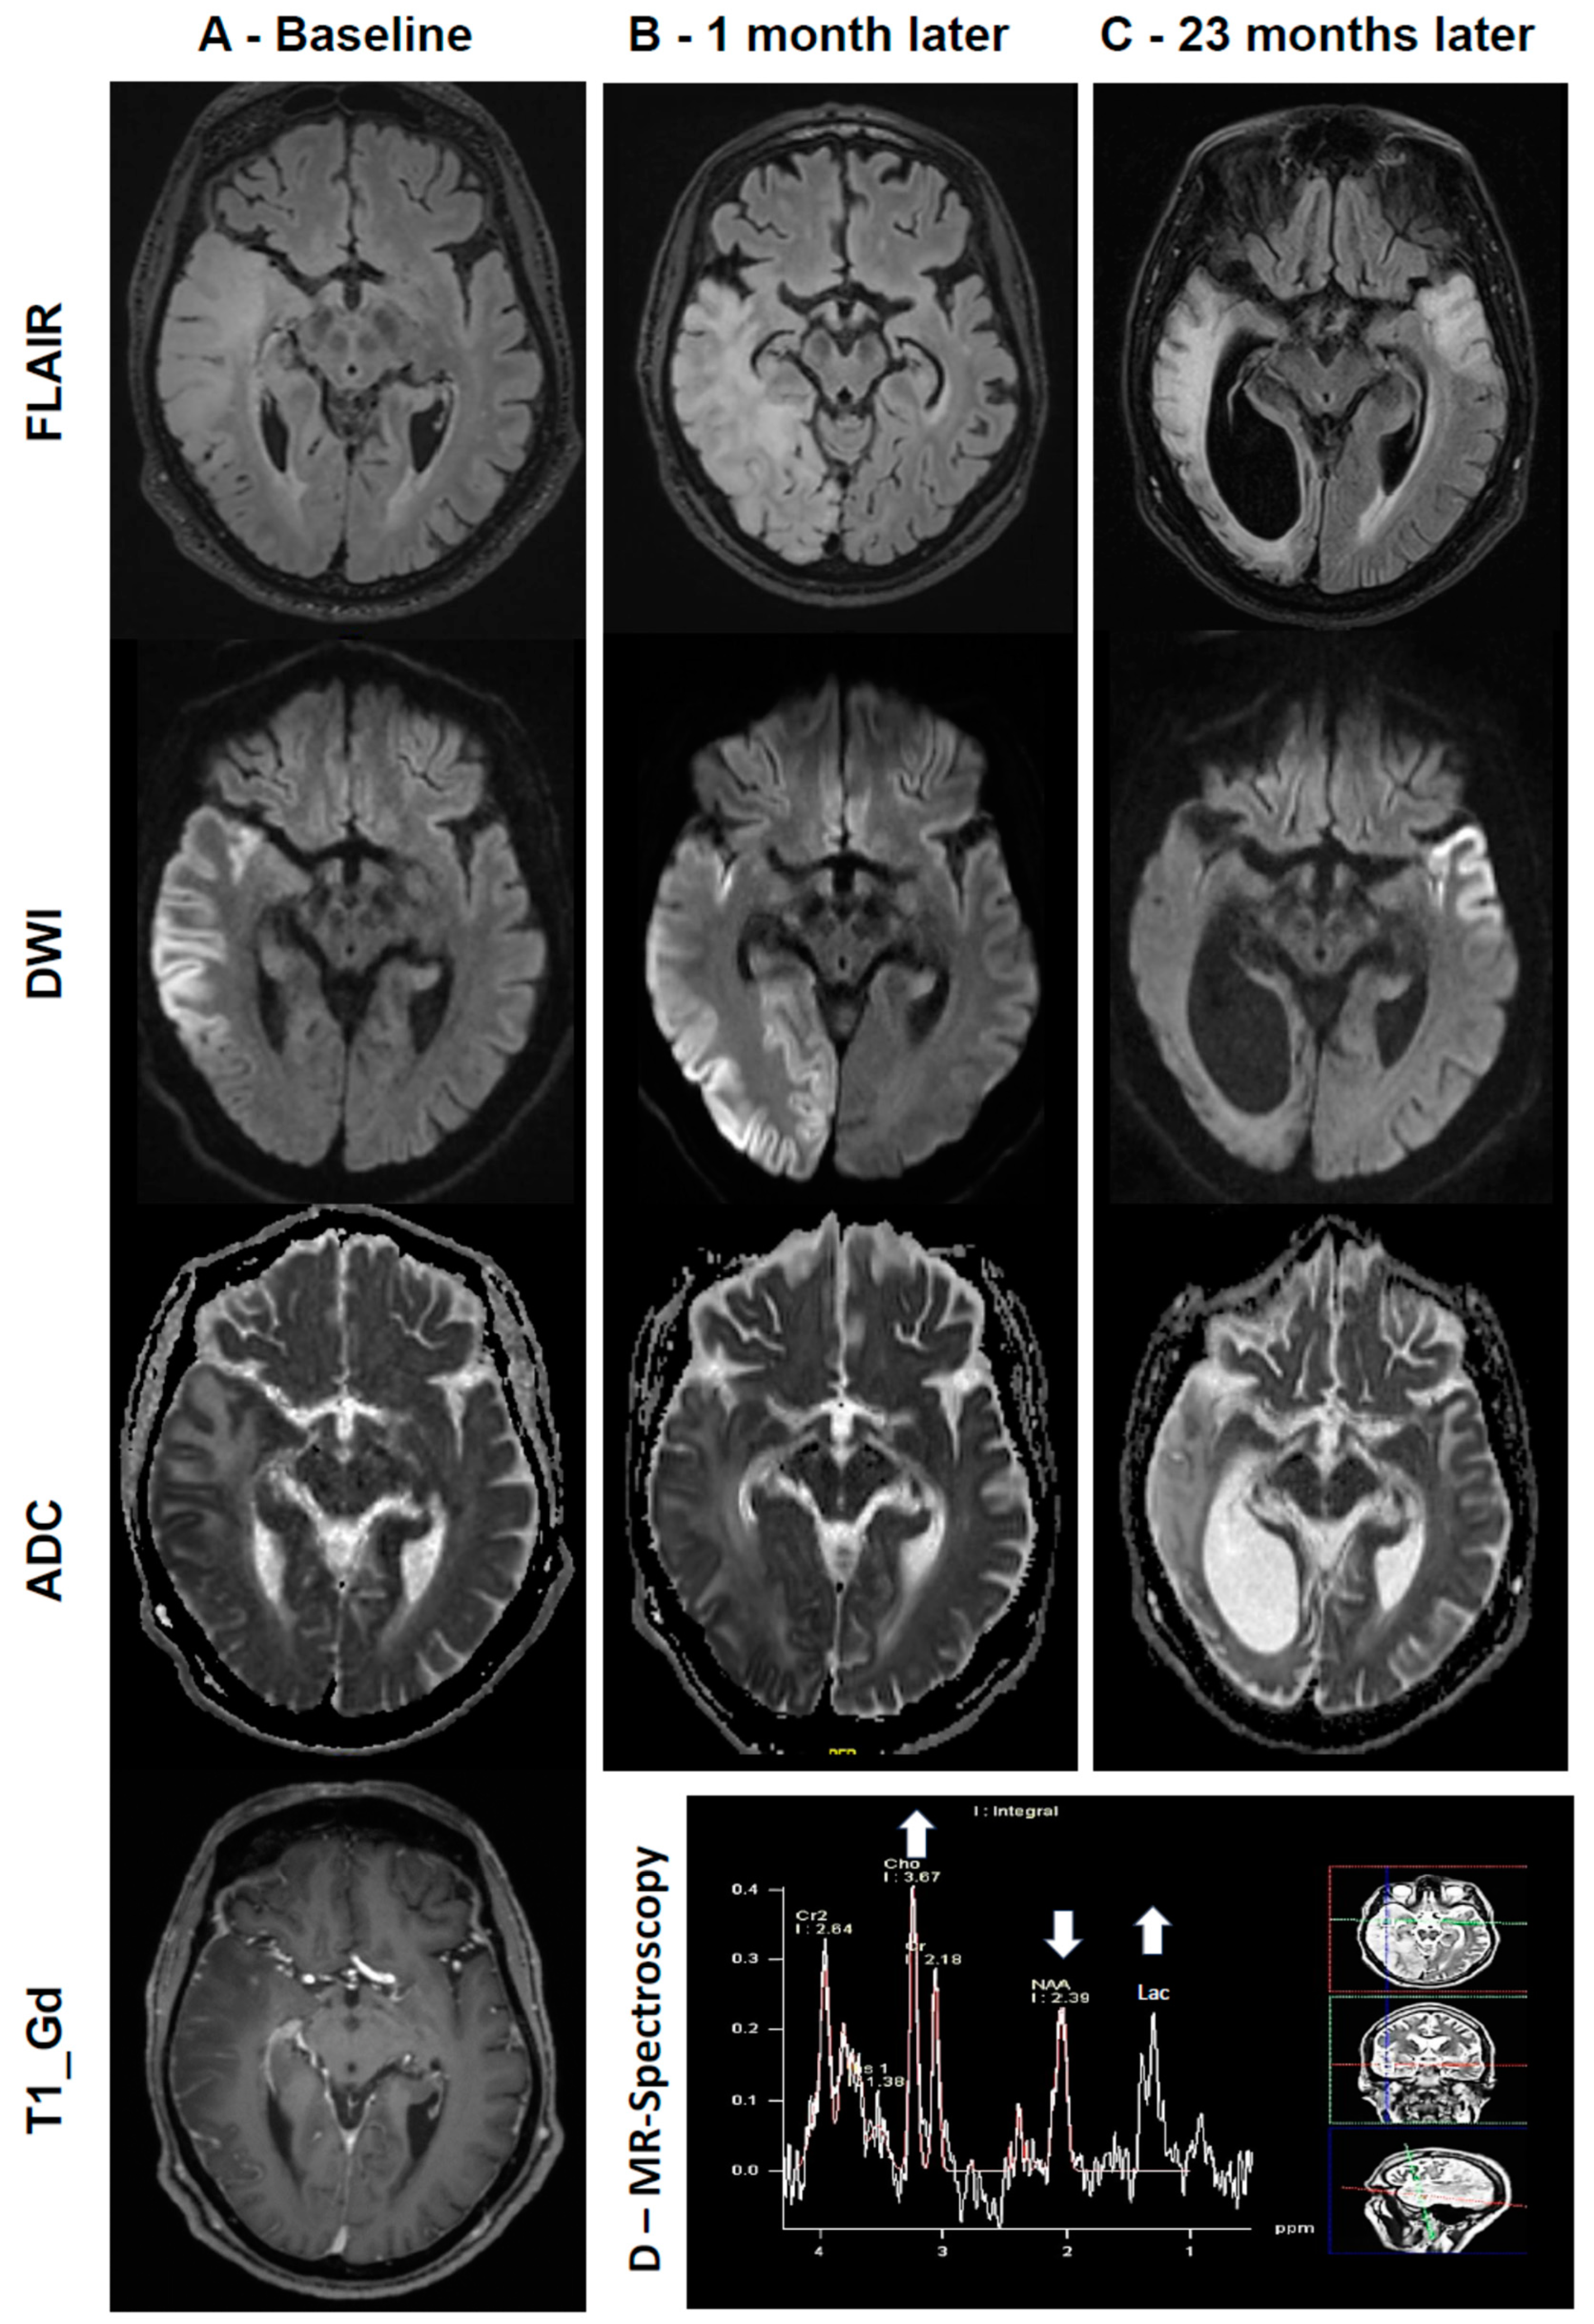

The next day, a contrast-enhanced MRI of the brain showed a cortical increased diffusion-weighted imaging (DWI) and fluid-attenuated inversion recovery (FLAIR) signal in the right temporal and parietal lobes with an associated subcortical edema. Apparent diffusion coefficient (ADC) maps revealed a reduction in ADC values in the right temporoparietal cortex, suggesting cytotoxic edema, but an increase in ADC values in the underlying subcortical white matter suggesting vasogenic edema. There was mild gyral contrast enhancement in the right temporal and parietal lobes visible in the T1-weighted and gadolinium-enhanced sequence (T1_Gd) (Figure 2A).

Figure 2.

(A) Brain MRI at first presentation (baseline). Top: the T2-weighted image (FLAIR) shows an extensive cortical/subcortical hyperintense lesion in the right temporal and parietal lobes. Upper and lower middle: DWI and ADC maps reveal an increase in DWI signals and a reduction in ADC values in the right temporoparietal cortex, suggesting cytotoxic edema, but an increase in ADC values in the underlying subcortical white matter, suggesting vasogenic edema. Bottom: the T1 gadolinium-enhanced image shows mild gyral contrast enhancement in the right temporal and parietal lobes. (B) Brain MRI at 1 month. Progression and expansion to the right occipital lobe (top: FLAIR; middle: DWI; bottom: ADC). (C) Brain MRI at 23 months. Chronic cortical/subcortical lesion on the right side with an associated marked ex vacuo dilatation of the right lateral ventricle. A new hyperintense FLAIR/DWI signal in the left temporal lobe (top: FLAIR; middle: DWI; bottom: ADC). (D) MR spectroscopy shows low N-acetyl aspartate (NAA) and high choline and lactate peaks in the right temporal lobe.

The patient’s mild progressive neurocognitive deficits did not resolve, and neither did the persistent left sensorimotor hemiparesis nor the hemineglect. One week after presentation, on a second MRI, there were clear signs of progression, so steroids were given empirically for 5 days (prednisolone 60 mg oral per day), without clinical improvement, however. The subsequent EEGs showed continuous slowing on the right-side temporal and parietal lobe, and there were no signs of epileptic activity; therefore, levetiracetam was stopped as the patient also developed aggressive behavior. Whole-body positron emission tomography/computed tomography with the glucose analog 2-[18F]fluoro-2-deoxy-d-glucose (FDG-PET/CT) revealed no neoplastic lesions, but a hypometabolism in the right temporal and parietal lobe. One month after presentation, a follow-up brain MRI showed signs of further progression and expansion to the occipital lobe (Figure 2B), and MR spectroscopy showed low N-acetyl aspartate (NAA) and high choline and lactate peaks (Figure 2D). A second steroid trial with methylprednisolone 1000 mg i.v. daily for 5 days again yielded no clinical response. As the patient’s symptoms had stabilized, therapy was not escalated to immunoadsorption or plasmapheresis. A cerebral corticosubcortical biopsy was performed and showed gliosis and microglial activation in the cortex and white matter, without evidence of inflammation or malignancy. Thus, both of these differential diagnoses could be excluded, and after almost 6 weeks, the patient was discharged to a rehabilitation center without a clear diagnosis but with a muscle biopsy scheduled during the second hospital stay.

- The repeated high lactate values in the CSF and MR spectroscopy raised the suspicion of mitochondrial disease, especially MELAS, despite there being no signs of typical clinical features such as diabetes, short stature, or hearing impairment.

Two years after diagnosis, the patient again developed rapidly progressive neurocognitive deficits with psychotic symptoms and CSF lactate acidosis. On this occasion, a brain MRI showed new DWI/FLAIR signals of the left temporal lobe (Figure 2C). We started high-dose L-arginine therapy (15,000 mg daily) over five days without clinical improvement. Zonisamide was stopped due to the possible worsening of metabolic acidosis. After a short referral to a psychiatric hospital, the patient’s symptoms improved slightly. The patient now lives in a nursing home, requiring assistance with the basic activities of daily living, but his overall condition has been stable for almost one year.